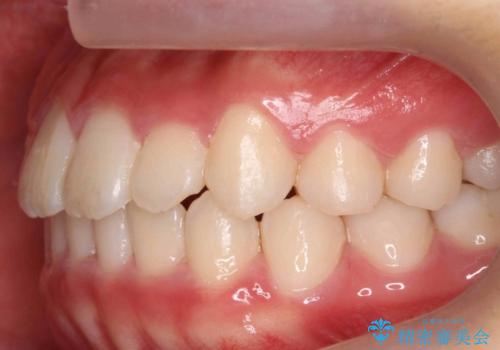

八重歯 歯を抜かずにインビザラインで

- 八重歯を主訴に来院。

抜かずに歯を少し削って入れる方法で並べました。

10代のうちに矯正をしておくと歯の移動は簡単で、歯ぐきも下がりにくいです。